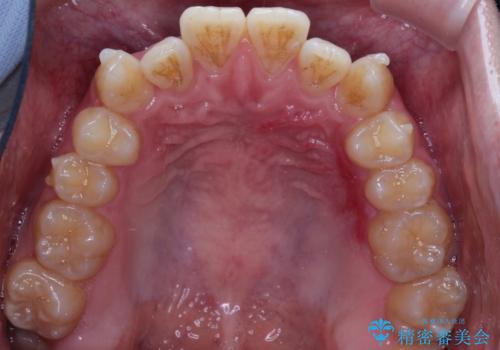

前歯のデコボコ インビザラインによる目立たない矯正

- 前歯のデコボコを主訴に来院された患者様です。

目立たないそうちをご希望されたので、インビザラインにて治療することとしました。

歯と歯の間をわずかに削ってスペースをつくり、デコボコを改善しました。